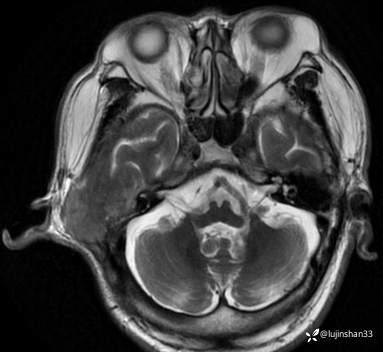

MRI:

简要病史:患者2022年10月掏耳后出现右耳疼痛,流水,伴血性分泌物,伴听力下降,无头痛头晕,无口角歪斜,自行购买滴耳液及口服罗红霉素,效果不佳。后右耳痛加剧,偶需止疼药治疗。后于XXXXXX医院行中耳乳突CT检查示“右耳恶性肿瘤?坏死性外耳道炎?”颅脑磁共振平扫示“脑内多发缺血灶、梗塞灶,脑白质疏松,脑萎缩、右中耳恶性占位。”建议上级医院治疗。2023-4-13就诊于我科门诊,行右外耳道病理活检示“鳞状上皮黏膜慢性炎伴急性炎,可见较多炎性坏死,部分上皮增生明显伴不典型增生,小灶上皮呈重度异型增生伴癌变。”建议手术治疗。今患者为求进一步诊治,门诊以“颞骨占位(右)“收治入院。

右侧颞骨鳞癌(T4)